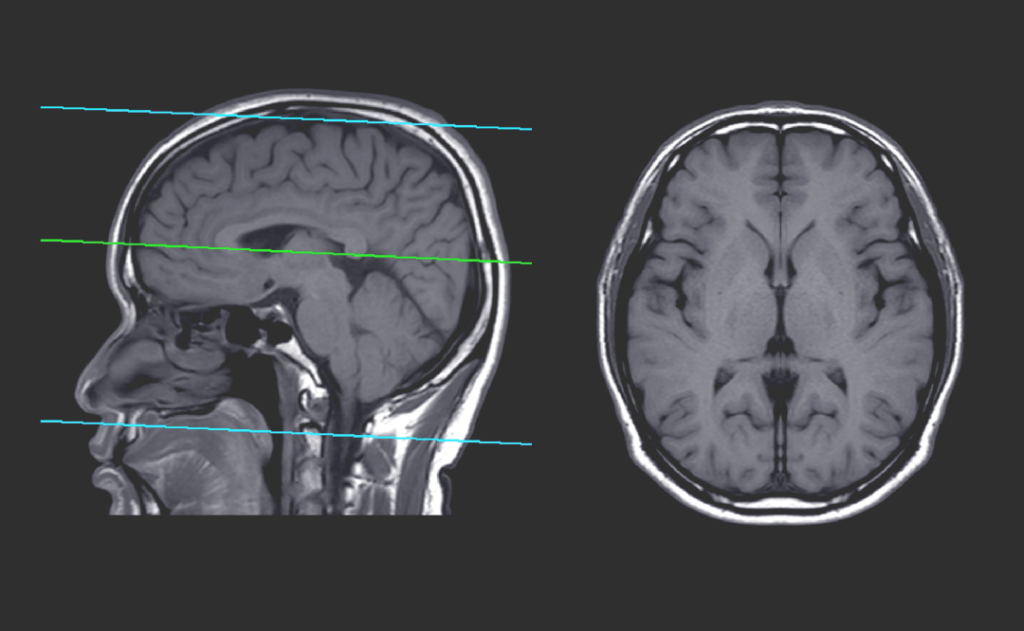

In CDI la Risonanza Magnetica Total Body viene eseguita con macchine interamente digitali di ultima generazione. La tecnica DWI (Diffusion Weighted Imaging), alla base dell’esame Total Body, garantisce risultati precisi e affidabili. Tale tecnica valuta la funzione molecolare e la struttura dei tessuti tramite l’analisi dei movimenti delle molecole d’acqua, mostrando una sensibilità ottimale nel […]

Il CDI dispone di apparecchiature innovative e ad alta tecnologia, completamente digitali, con sequenze ottimizzate per garantire indagini Total Body affidabili. Va ricordato che tutte le apparecchiature RM ad alto campo eseguono esami di tipo diagnostico; non tutte, però, sono in grado di eseguire RM TotaI Body affidabili. Inoltre, oltre alla tecnologia d’avanguardia, è previsto […]